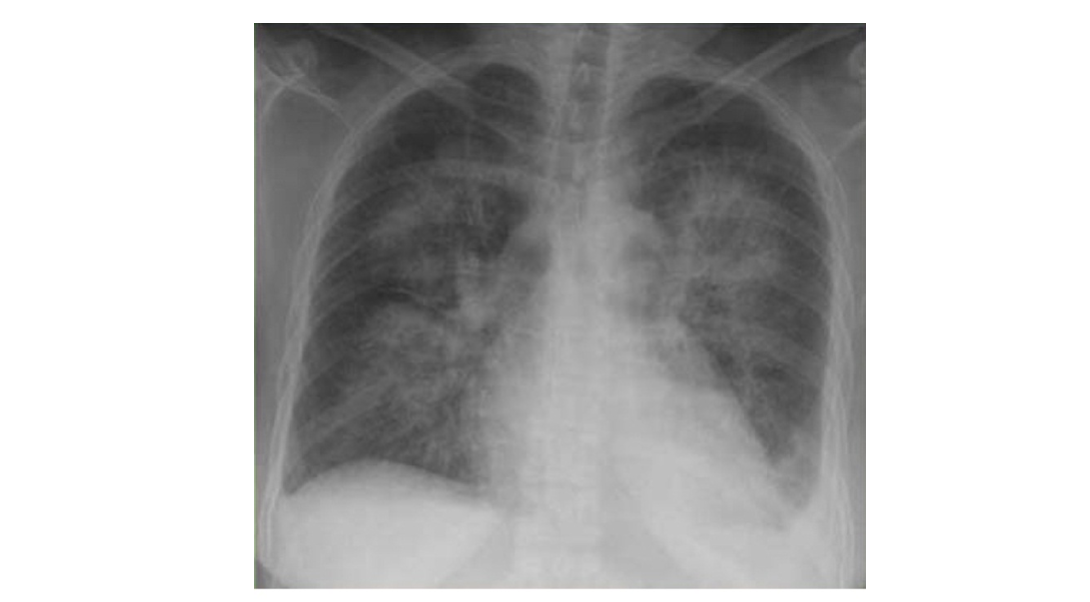

ការថតទ្រូងប្រើដោយកាំរស្មីអ៊ិច (chest x-ray) គួរតែប្រព្រឹត្តទៅបានដើម្បីស្វែងរកភ័ស្តុតាង នៃជំងឺហើមសួត (pulmonary edema) និងជំងឺស្ទះសរសៃឈាមនៅក្នុងសួត (pulmonary vascular congestion)។

ទំហំរបស់បេះដូងអាចដឹងបានតាមរយៈការថតទ្រូងប្រើដោយកាំរស្មីអ៊ិច (chest x-ray)។ នៅក្នុងជំងឺខ្សោយបេះដូងរាំរ៉ៃសាច់ដុំបេះដូងជារើយៗ តែងតែកើននូវទំហំក្នុងគោលបំណងដើម្បីច្របាច់ឈាមអោយបានល្អគ្រប់គ្រាន់។ ទោះយ៉ាងណាក៏ដោយទំហំរបស់បេះដូងធំធ្វើអោយជំងឺខ្សោយបេះដូងកាន់តែធ្ងន់ធ្ងរថែមទៀត។ ការដែលបេះដូងរីកធំហៅថា cardiomegaly។